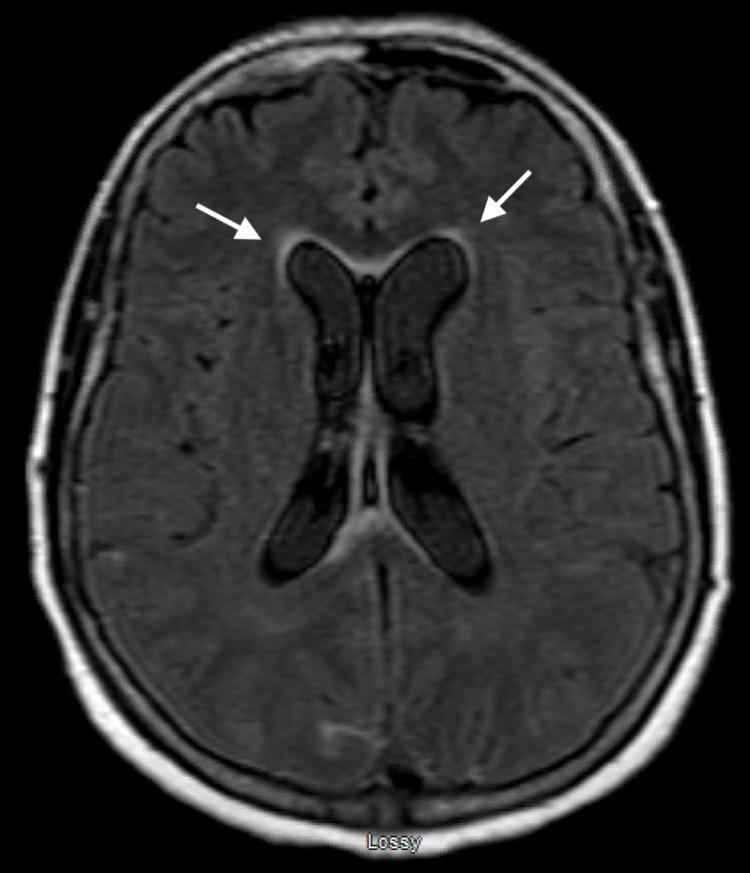

A preliminary report warned that severe acute respiratory syndrome coronavirus 2 (SARS-CoV-2) could have neuro-invasive potential as it was observed that some patients showed neurologic symptoms such as headache, nausea, and vomiting. Following early speculation there have been reports of neurologic manifestations involving both the central nervous system and peripheral nervous system including reports that coronavirus disease 2019 (COVID-19) may increase the risk of acute ischemic stroke. Here we present a patient with recent COVID-19 infection who experienced low-pressure hydrocephalus requiring high-output cerebrospinal fluid (CSF) diversion following spontaneous angiogram-negative subarachnoid hemorrhage. We hypothesize that patients who are either currently or who have recently been infected with SARS-CoV-2 may have altered ventricular compliance and/or altered CSF hydrodynamics from mechanisms that are not yet understood but potentially related to previously described pathophysiologic mechanisms of the virus and associated inflammatory reaction.

一份初步报告警告称,严重急性呼吸综合征冠状病毒2(SARS-CoV-2)可能具有神经侵袭潜力,因为观察到一些患者出现头痛、恶心和呕吐等神经症状。在早期猜测之后,有报道称神经系统表现涉及中枢神经系统和周围神经系统,包括有报道称2019冠状病毒病(COVID-19)可能增加急性缺血性中风的风险。在此,我们报告一名近期感染COVID-19的患者,该患者在自发性血管造影阴性蛛网膜下腔出血后出现低压性脑积水,需要进行高流量脑脊液(CSF)分流。我们推测,目前或近期感染SARS-CoV-2的患者可能存在心室顺应性改变和/或脑脊液流体动力学改变,其机制尚不清楚,但可能与该病毒先前描述的病理生理机制及相关炎症反应有关。